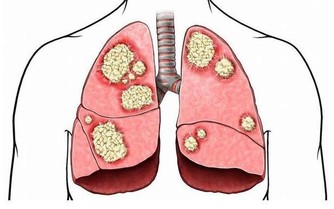

結腸癌症狀

5、晚期表現

晚期出現肝轉移的時候會出現黃疸、腹水、浮腫以及惡病質。